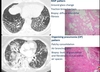

NSIP pattern?

* ground glass change * traction bronchiectasis * biopsy: diffuse interstitial fibrosis

Organising pneumonia pattern?

* patchy consolidation * air bronchograms * biopsy: buds of granulation and fibroblastic tissue within air spaces